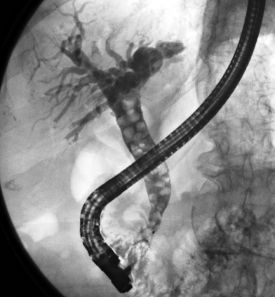

Die ERCP (endoskopisch retrograde Cholangio-Pankreatikographie) ist eine Untersuchung der Gallengänge und des Bauchspeicheldrüsengangs. Dazu wird ein biegsames optisches Instrument (Duodenoskop) über die Mundhöhle, Speiseröhre und Magen in den Zwölffingerdarm vorgeschoben. Dort befindet sich die Mündung von Gallen- und Bauchspeicheldrüsengang, die hierbei mittels Röntgen untersucht werden kann.

Wie läuft eine ERCP ab?

Die Untersuchung wird in Bauchlage durchgeführt. Aus Sicht des Patienten ähnelt sie der Magenspiegelung, allerdings wird das Endoskop tiefer in den Zwölffingerdarm platziert, so dass die Gallengangsmündung (Papille) zu sehen ist. In diese wird Kontrastmittel eingespritzt, und so die Gallengänge unter Röntgendurchleuchtung sichtbar gemacht.

Ist beispielsweise ein Abflusshindernis in den Gängen durch Gallensteine vorhanden, kann dies nun endoskopisch mit verschiedenen Methoden beseitigt werden.